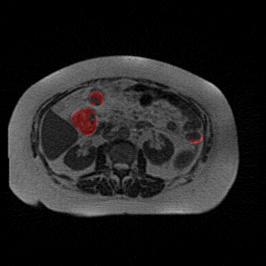

Bias Field Artifact

MRI GMAIMMbench Organ Recognition - Abdomen

Bias Field Artifact - L0 (Original)

L0

L0 (Original)

Question

Observe the MRI image. Can you identify the organ in the highlight area?

A fat B stomach C optic cup D gallbladder E optic disc

Ground Truth: B. stomach